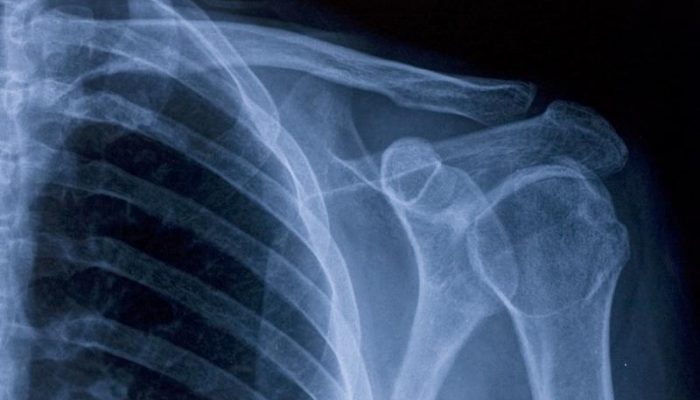

Чтобы понять, почему болит рука от плеча до локтя, предплечье или кисть, необходимо провести дополнительную диагностику. Лишь на основании клинического осмотра трудно сделать верное заключение – врач должен подтвердить свое предположение инструментальными и лабораторными методами. К таковым относят:

- Рентгенографию.

- Томографию (магнитно-резонансную и компьютерную).